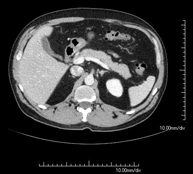

- TC Abdomen

Prueba diagnóstica que consiste en obtener imágenes del abdomen de alta definición anatómica (hígado, vesícula biliar, vía biliar, páncreas, bazo, estómago, intestinos, riñones, estructuras vasculares, vejiga, útero y ovarios, etc.) mediante el empleo de un equipo de TC (Tomografía Computarizada). Dichas imágenes se estudian posteriormente en una estación de trabajo que permite reconstrucciones bidimensionales en diferentes planos del espacio, y también reconstrucciones 3D (volumétricas). La mayoría de estudios requieren el empleo de contraste yodado para mejorar la definición de las imágenes.